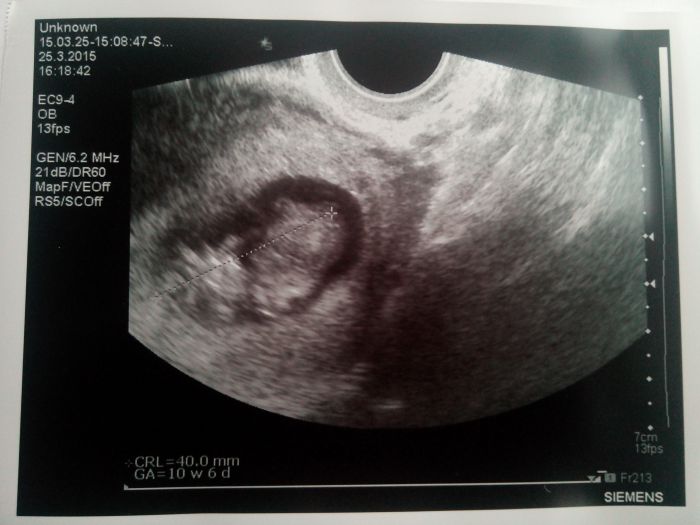

Ahoj devcata :-) dnes jsem mela byt 11+2 ale podle ultrazvuku jsme zase o 3 dny menší, takže se zase posouvám na 10+6 :o) misto 1cm pred měsícem máme už 4cm :) doktor myslel ze mi uz dnes udela screening a zitra mě pošle na krev a museli jsme to odlozit na pristi tyden :-) fazolka je ale čilá,kopala,cucala si paleček a pořad se na ultrazvuku předvádela :-)))...ale od nedele me trápí skrípnutý sedací nerv a doktor říkal že je to kvůli zvětšující děloze a že mám ležet s nohama nahoru :o) mam s tim teda problemy uz od prvniho porodu takze vim že leženi mi pomůže ale doufám že nebudu ležet třeba měsíc...:-)